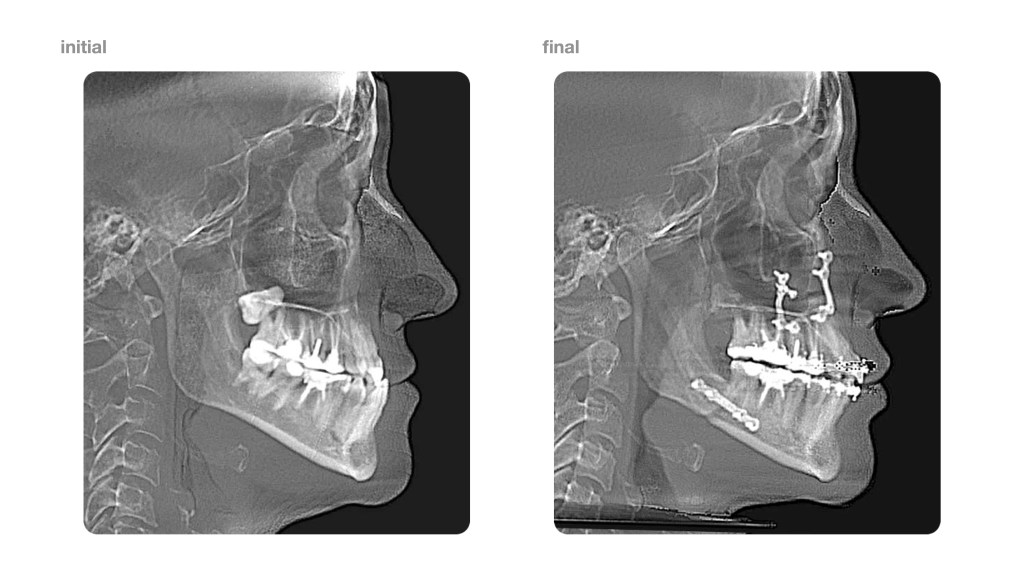

Below is my recently finished case which seems to be in agreement with the figures provided by the authors.

Surgery is performed by Dr. Andrey Senyuk at Face Smile Center in Moscow, Russia.